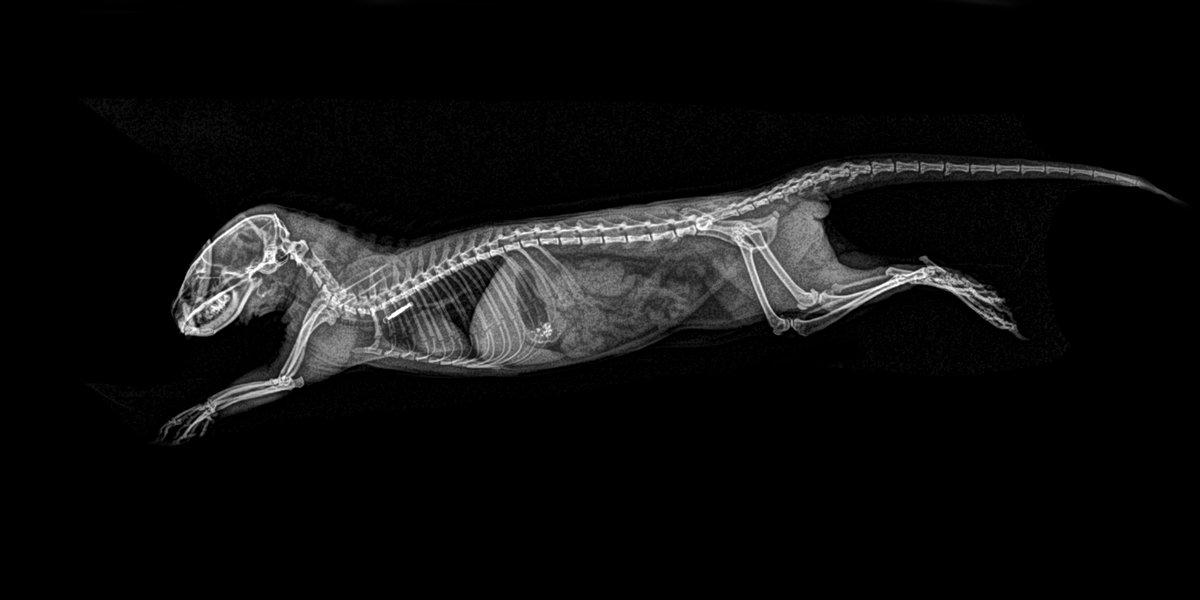

Mangosta